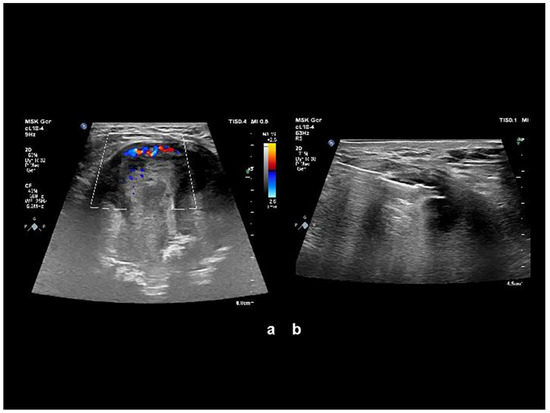

The combination of aggressive bone destruction, lesion extending into the pelvis, and a non-aggressive sclerotic margin with a narrow zone of reactive osteosclerosis were considered controversial. A significant portion of the lesion infiltrated the gluteal muscles, displaying subtotal central necrosis and a thin viable (enhancing) rim preserved in the periphery. Calcification of an unusual morphology was visible in the center of the lesion. Bone destruction associated with soft tissue mass and an irregular tumor shape suggested a malignant lesion. Ultrasound assessment and ultrasound-guided needle biopsy followed (Figure 2).

Figure 2. (a) Color Doppler imaging sonography revealed inhomogeneous expansion with alternating major and minor hyperechogenic areas, with portions significantly hypervascularized and completely without hypervascularization. (b) Ultrasound-guided needle biopsy focused on viable tissue was performed. At the puncture, the expansion capsule was rigid and “fibrous”.